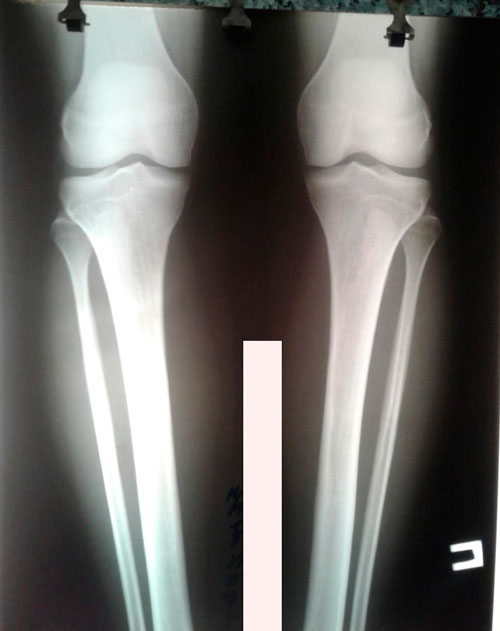

Исходник- 34 года.

Дата снятия аппаратов - 20.08.2019г.

Срок сращения - 102 дня.